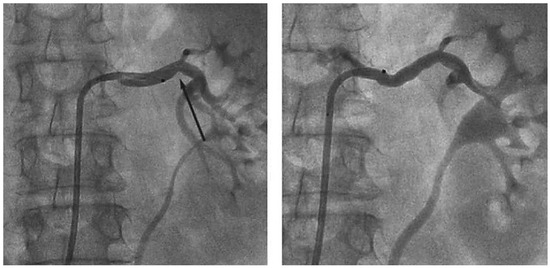

Case report A 22-year-old male experienced a presyncopal spell while studying for a university examination [...]